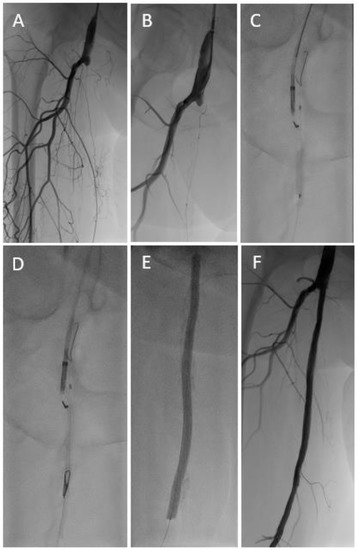

Figure 2.

In a patient with critical limb ischemia and femoropopliteal occlusion (A,B), conventional recanalization attempts of the native artery and the chronically occluded femoropopliteal vein graft (C) were unsuccessful. Finally, target balloon-assisted re-entry with a retrogradely inserted GoBack™ catheter (D) enabled successful wire passage and adjunctive therapy of the native femoropopliteal segment (E–G) with a single-vessel run-off (H).